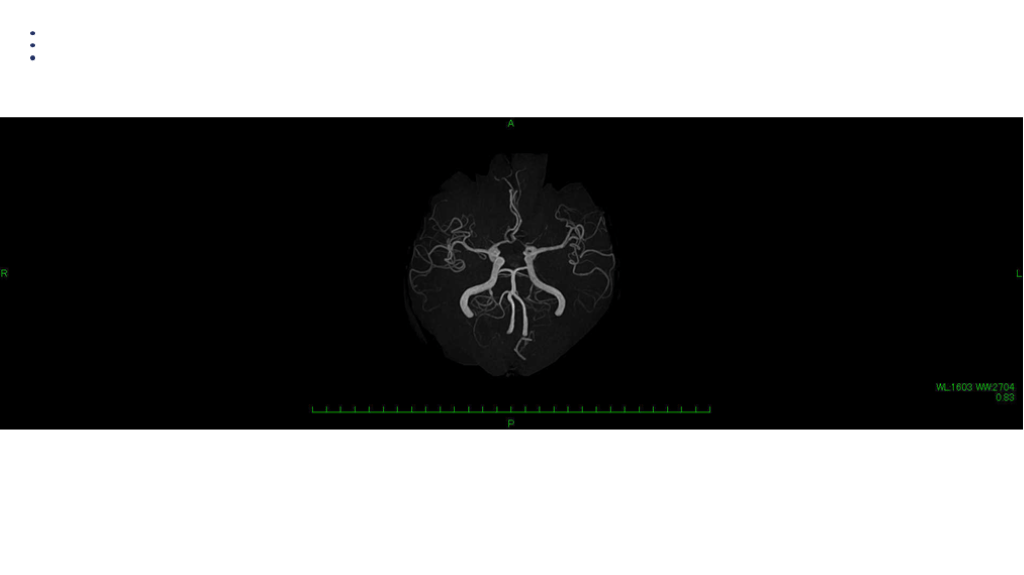

画像 所見 DAY 14 MRA 悪化